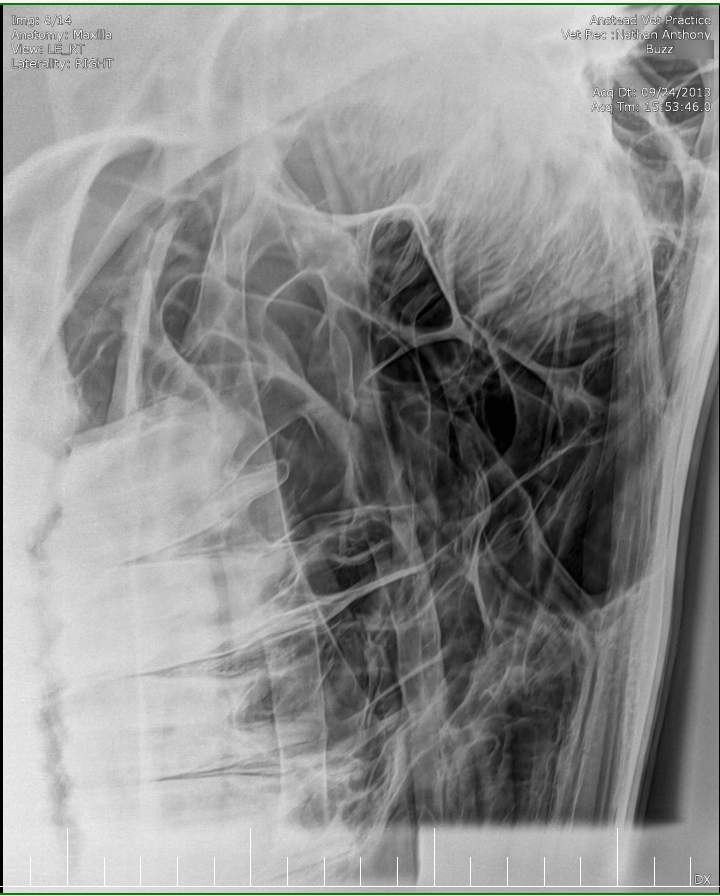

Posted on Sunday, May 8, 2016 - 6:24 pm: Thank you for the welcome!I did contact the lab to see if they still had the samples but they will only speak to the vets who submitted the samples. I've asked my vet to ask on my behalf but haven't yet heard back yet. The horse has been scoped and I was told that it all looked normal. The stylohoid bone and guttural pouches normal. The inflammation is mostly around the nostrils as per the pic but there are a couple of small spots further up inside the nose. He's also had his skull xrayed which I'm told also looked normal. I've included the pics at the bottom. I've included a list of other things here that have been tested to see if they influence the shaking or inflammation for the better or worse: - experimental course of Equity - Flixotide via inhaler - high dose of prednisolone - did work! - low dose of prednisolone - did not work - teeth checked by two different vet dentists - fly masks & nose nets - relocated him to several different places in the city incase it's an environmental allergen - all sorts of feed supplements - removed all hard feed, just feeding hay - stabled him 24/7 and fed him Haygain steamed hay incase it was something in the paddock - light/dark makes no difference to the shaking - it's not seasonal, happens year round I've also had bloodwork done and it showed a low red blood cell count. The blood was taken two weeks after the biopsies. My vet didn't think the low count was attributed to the blood loss from the biopsies so he suggested parasites but a worm count came back clean. I also had a test to see if there was blood in the manure, but nothing was found. There was no plan made to address the low RBC. Results are attached in a text file to maintain the spacing.

Xray images: